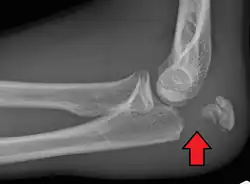

Olecranon fracture is a fracture of the bony portion of the elbow. The injury is fairly common and often occurs following a fall or direct trauma to the elbow. The olecranon is the proximal extremity of the ulna which is articulated with the humerus bone and constitutes a part of the elbow articulation. Its location makes it vulnerable to direct trauma.

To assess an olecranon fracture, a careful skin exam is performed to ensure there is no open fracture. Then a complete neurological exam of the upper limb should be documented.[5][2] Frontal and lateral X-ray views of the elbow are typically done to investigate the possibility of an olecranon fracture.[1] A true lateral x-ray is essential to determine the fracture pattern, degree of displacement, comminution, and the degree of articular involvement.